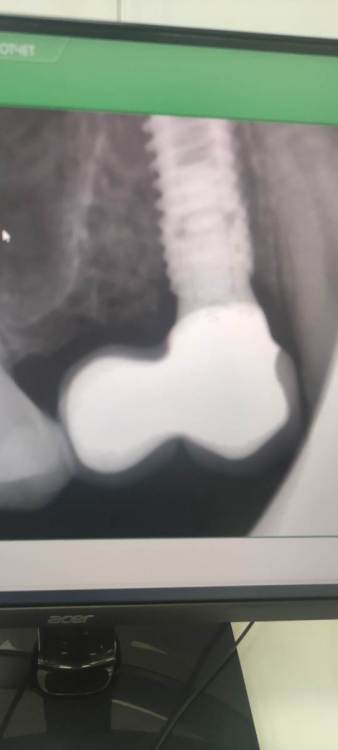

NazranDantist Опубликовано 20 октября, 2023 Поделиться Опубликовано 20 октября, 2023 Это примерно пол года прошло, самый старый снимок:) Это переимплантит, минус два разом). При этом выкрутились с трудом МЮ ленмириот угловые 1 1 Ссылка на комментарий

NazranDantist Опубликовано 20 октября, 2023 Поделиться Опубликовано 20 октября, 2023 И прямые МЮ 1 Ссылка на комментарий